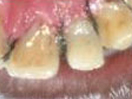

Dead discolored tooth

with a growth in bone

Treating Non-Vital Tooth with Apical Pathology with the help of MTA

In the process of

saving tooth by

Root Canal Treatment

MTA is placed in

the apical 5mm

of Root Canal.

Rest part kept empty.

A Glass Fiber post is the process of being fixed within empty

part of Root Canal with the help of Composite Resin.

Tooth is prepared for receiving a crown.

X-ray after Preparation

The Smile after placing

the Temporary Crown.